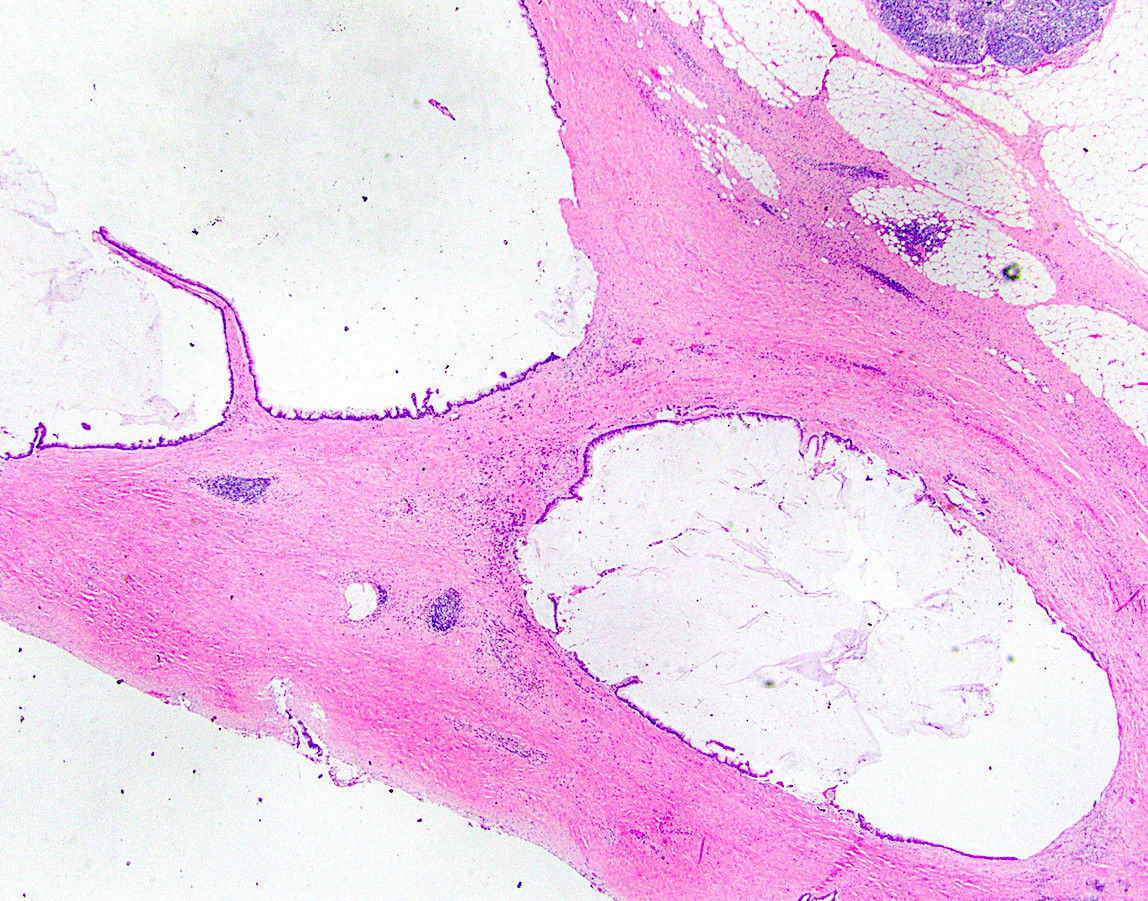

Microscopic (histologic) description

- Villous or occasionally flat proliferation of mucinous epithelial cells originating from appendiceal lumen

- Lesional cells typically demonstrate abundant apical mucin with elongated nuclei and low grade nuclear atypia (LAMN); however, nuclei may appear compressed or rarely high grade (HAMN)

- Often associated with atrophy of underlying lymphoid tissue, crypt loss and effacement of muscularis mucosae

- Broad dissection of mucin, epithelium or both may occur with potential involvement of extra-appendiceal surface, an important finding affecting prognosis

- Extra-appendiceal mucin incites a serosal reaction and may contain neovascularization, assisting in differentiation from benign transfer of mucin during gross examination

Microscopic (histologic) images

Contributed by Raul S. Gonzalez, M.D. and Michael Feely, D.O.